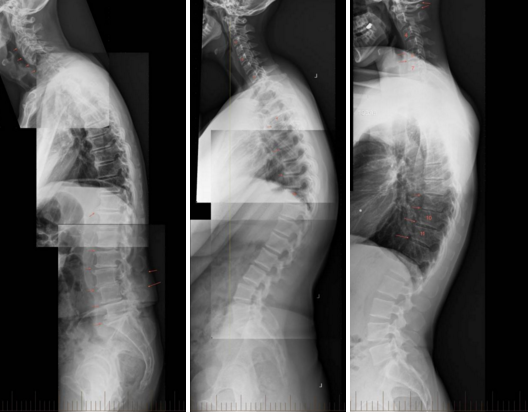

Kështu doktor Carter, për të sqaruar sa më mirë dhe për të vedijësuar të gjithë në lidhje me situatën e krijuar nga përdorimi i tepërt i celularëve e mjeteve të tjera teknologjike, ka sjellë edhe fotografi të boshteve kurrizore të disa fëmijëve të cilët ai i ka kontrolluar gajtë punës së tij.

Ai thotë: “Ja shikoni ne foto në vend se të kenë një kurriz normal përpara, pacientët e mi fëmijë, shihet qartë se kanë një kurriz të dëmtuar e që tërhiqet pas. Kjo është shumë degjenerative që shkakton dhimbje të pandalshme të kokës, qafës, shpatullave e të të gjithë pjesës shpinore gjithashtu’’.